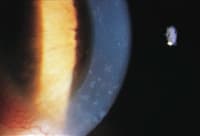

Figures 1a and 1b. Patient's right eye at the time of his initial presentation. |

The patient presented with a three-day history of red eyes, mild discomfort and a decreased wearing time. Slit lamp examination revealed 2+ conjunctivial injection, diffuse corneal edema, 360 degrees of peripheral neovascularization and multiple peripheral and mid-peripheral infiltrates (Figures 1a, 1b, 2a and 2b).